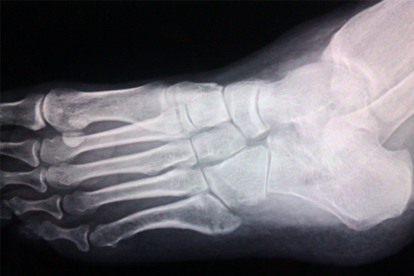

拇外翻治療后需進(jìn)行系統(tǒng)康復(fù)管理,術(shù)后早期應(yīng)抬高患肢減輕腫脹,按時(shí)更換敷料保持傷口清潔。拆除固定后需循序漸進(jìn)開展關(guān)節(jié)活動(dòng)度訓(xùn)練,避免僵硬。穿戴專用足踝支具4-6周提供外部支撐,定制矯形鞋墊糾正生物力學(xué)異常??祻?fù)期間避免長時(shí)間站立和劇烈運(yùn)動(dòng),選擇鞋頭寬松的軟底鞋。定期復(fù)查X線片評(píng)估愈合情況,出現(xiàn)紅腫熱痛需及時(shí)就醫(yī)。良好的康復(fù)護(hù)理能鞏固治療效果,降低復(fù)發(fā)概率。